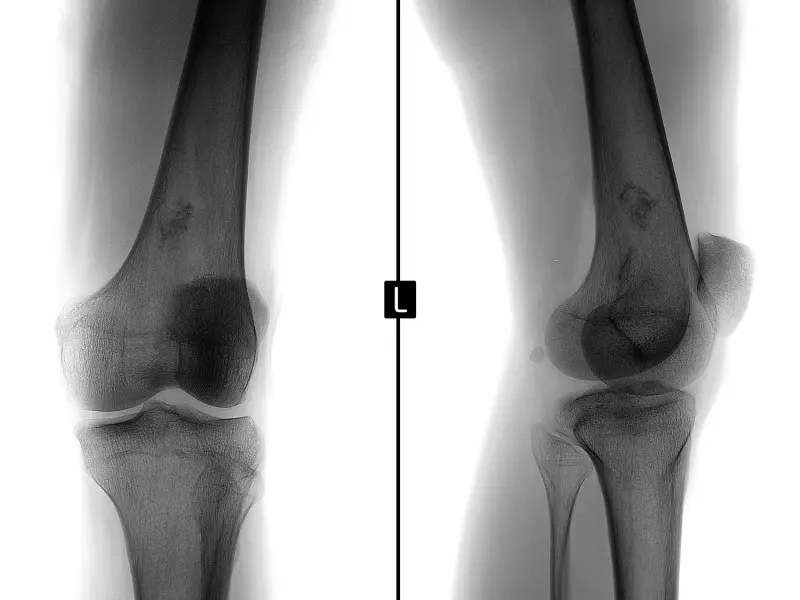

Postępowanie fizjoterapeutyczne po podaniu komórek macierzystych CD34+ w przebiegu choroby zwyrodnieniowej stawów narządu ruchu część 2

Narząd ruchu człowieka poprzez swoją skomplikowaną budowę anatomiczną i złożoną biomechanikę staje się bardzo podatny na różnego rodzaju urazy. Wszelakie kontuzje przydarzają się nie tylko ludziom aktywnie uprawiającym określone dyscypliny sportowe, ale coraz częściej osobom niemającym żadnych powiązań z aktywnością ruchową. Ważna w tym względzie jest szeroko promowana nowoczesna specjalistyczna fizjoterapia.